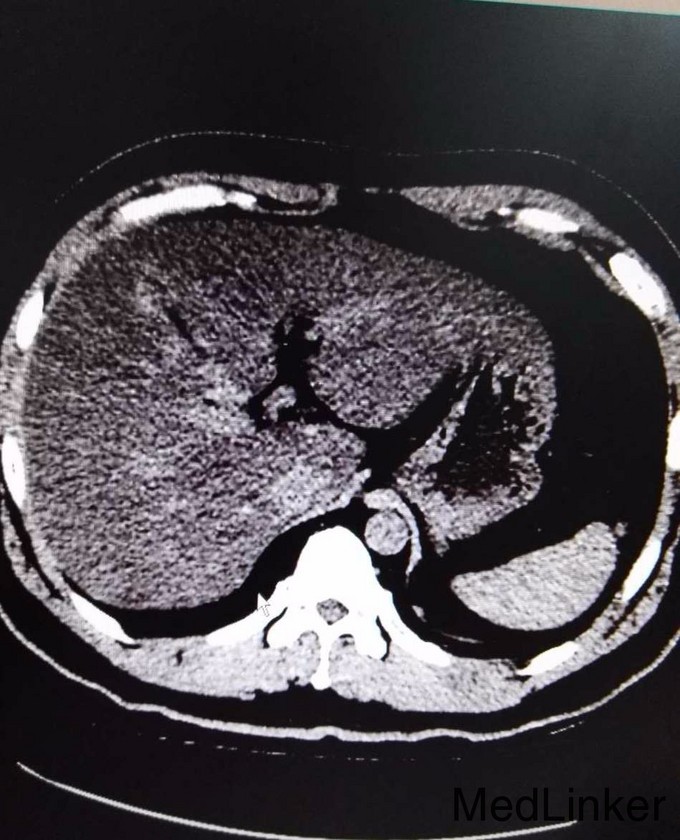

3、入院诊断:肾积水伴输尿管结石(左侧),治疗:入院后完善相关检查,尿常规GLU 2+,生化GLU 6.58,KUB考虑左侧输尿管下段结石可能,CT示左侧输尿管下段近膀胱入口处结石,重度弥漫性脂肪肝,其余检查无特殊,行左输尿管镜检+钬激光碎石术,术中放置DJ管,术后给予抗感染、对症支持治疗。术后患者恢复良好,复查KUB DJ管在位,未见异常。